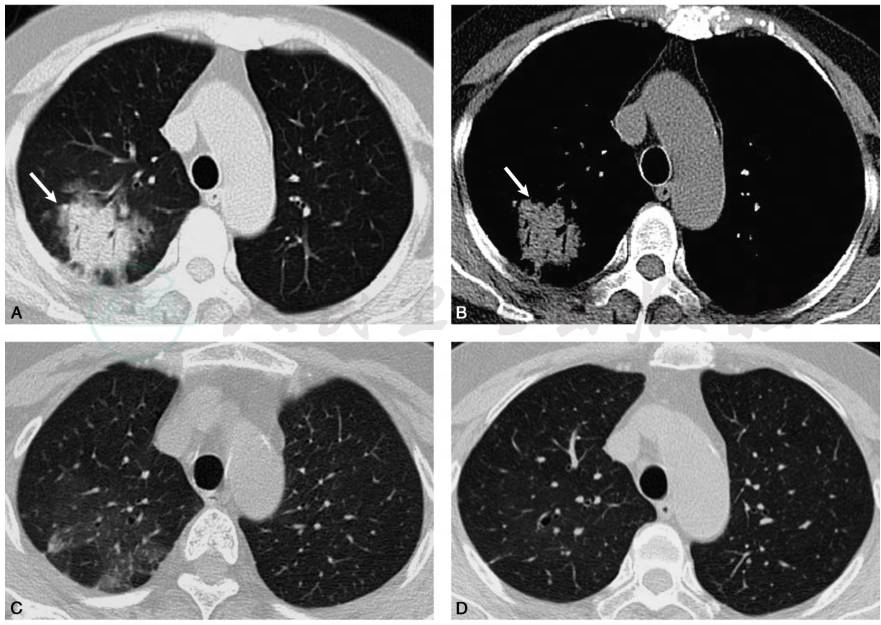

2018年1月初患者无明显诱因下开始出现干咳、流清涕,伴低热,最高达37.9℃。2018年1月18日患者就诊于社区医院,给予氨麻美敏片、蛇胆川贝液口服后咳嗽、发热症状不缓解。2018年2月7日患者就诊于我院呼吸科,复查胸部CT(图4A、B):右肺上叶模糊影,部分致密,建议治疗后复查;左肺下叶纤维条索。给予对乙酰氨基酚退热,头孢克洛抗感染后,患者咳嗽、发热症状仍不缓解。遂再次收入院进一步治疗。综合以上检查结果考虑隐源性机化性肺炎复发。再次给予泼尼松30mg/d口服,1个月后门诊复查,患者症状消失,胸部CT显示病灶明显吸收消散(图4C);随后根据患者症状和胸部CT表现逐渐减量,最后小剂量5mg长期维持,每2~3个月门诊随访,2018年7月16日复查胸部CT示:右肺上叶病灶完全吸收(图4D)。

图4 患者激素停药后2个月新发咳嗽、气短伴发热,胸部CT检查可见右肺上叶实变伴支气管充气征,周围有磨玻璃影(A、B白箭);再次使用激素30mg治疗1个月余,复查胸部CT提示右上肺病灶明显吸收,残留少许磨玻璃影(C);激素减量口服5个月,复查胸部CT示右肺上叶病灶完全吸收(D)